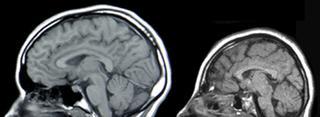

Человек фло́ресский — возможный карликовый вид ископаемых людей. Из-за малого роста флоресский человек известен также как «хоббит». Останки Homo floresiensis обнаружены в 2003 году в Индонезии, где найдены несколько скелетов разной степени сохранности возрастом приблизительно в 13—95 тысяч лет. По единственному известному черепу и наиболее полно сохранившимся скелетам рост флоресских людей оценивается примерно в 1 м, а объём головного мозга в 400 см³, что в три раза меньше объёма мозга современного человека и приближается к параметрам, характерным для австралопитеков. Исследователи отмечают также многочисленные архаичные черты в строении черепа и конечностей флоресских людей.